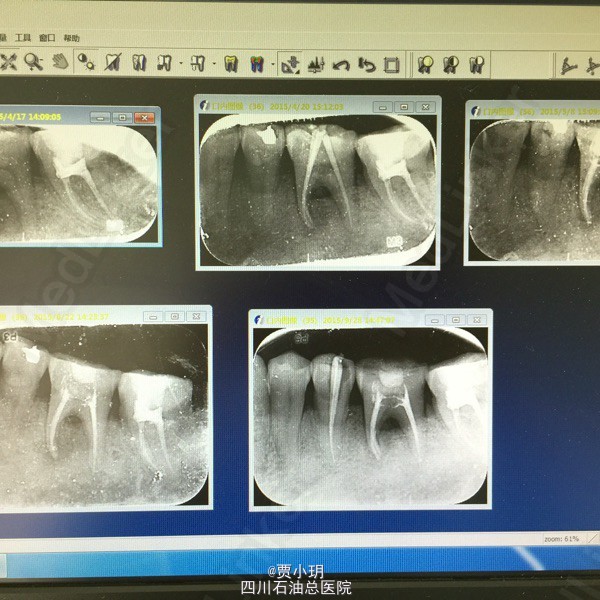

随访:患者根充后一个月复诊,未有任何不适,查体可见36松动I度-,叩痛(-),颊侧牙龈略有退缩。X线示36根周阴影范围明显缩小,骨密度有所增加。拟三个月后复诊。 今日患者根充后四个月复诊,拍片可见根周和根分叉的炎症已经明显控制,骨密度良好,但是根分叉的骨吸收还是存在。且患者目前无任何临床不适,查体见36松动度(-),根分叉探及无牙周袋,牙龈附着良好。 讨论:其实刚开始对这颗牙的治疗没抱太大希望,因为初诊情况太差,但该患者保留意愿很强烈,而且配合度很好。而且以前没有尝试过牙周方面的治疗。其实如果牙周治疗方面能更严谨和完善,可能效果会更好,比如对颊侧牙龈附着的恢复和骨再生。下面是每次治疗的对比图。

今天患者根充后两年复诊,期间未出现任何临床症状,根分叉处探诊结果良好,X片示近中根周以及炎症区已经完全恢复,牙周膜清晰可见,而且根分叉处的骨质居然有增长迹象。